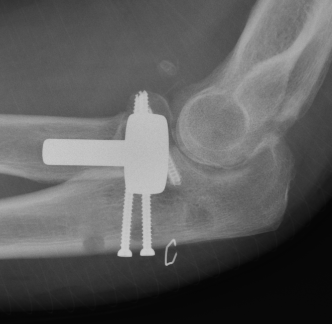

Medial approach and buttress plate with LCL repair

buttress plate

Universal posterior approach with radial head replacement and medial approach with medial buttress plate